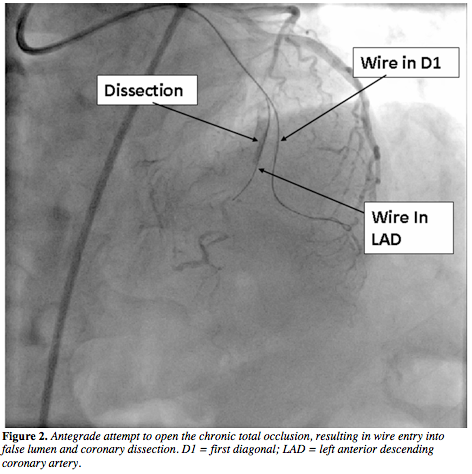

us for coronary angiography and possible revascularization. His electrocardiogram was unremarkable and an echocardiogram showed normal left ventricular function. Coronary angiography revealed left dominant coronary circulation and a long CTO segment in the mid-LAD (Figure 1 and Video 1). The distal segment of the LAD was supplied via an ipsilateral intraseptal collateral channel (Figure 1). The CTO segment was very long and the entrance to the occlusion had an unusual configuration. After a lengthy struggle using the antegrade approach, a Conquest Pro guidewire (Asahi Intecc) successfully penetrated through the proximal segment. Consequently, a large false lumen was created, but the distal true lumen could not be

negotiated (Figure 2). The procedure was eventually abandoned. An ipsilateral intraseptal collateral channel was comparatively straight for better accommodation of the retrograde wiring. A second attempt using retrograde approach was thus made after 2 months. A 7 Fr Launcher 3.5 guide catheter (Medtronic, Inc) was engaged in the left coronary artery and a Fielder FC 300 cm guidewire (Asahi Intecc) was introduced in the proximal septal branch and navigated into the distal LAD through the distal septal branch via intraseptal collateral (Figure 3). Because of its favorable angulation and low tortuosity, wire manipulation in the distal LAD was relatively smooth. The retrograde guide catheter was cut short for longer distance to the lesion.